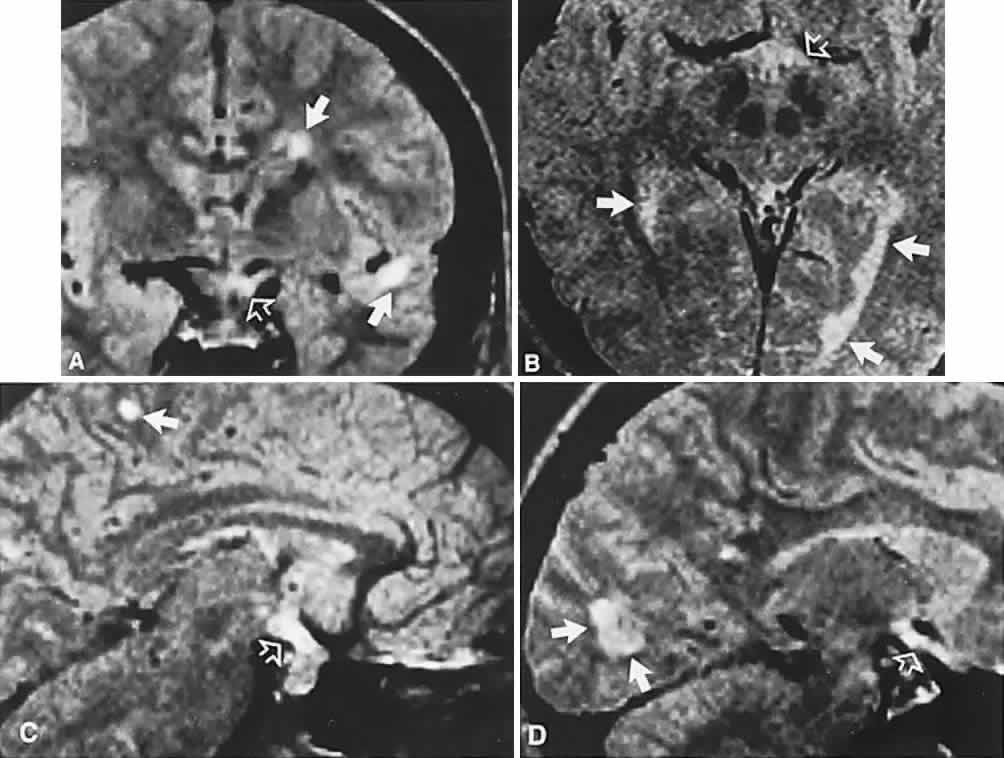

CT scanning retains special relevance to craniopharyngioma diagnosis, currently superior to MRI in detection of calcification and cyst formation (Fig. 7A to C); however, the extent of involvement of adjacent structures, that is, the optic chiasm, third ventricle, and intracavernous carotid artery, is more clearly delineated by MRI (Fig. 7D and E).93 Craniopharyngioma fluid collections are found to be uniformly bright on T2-weighted sequences, but on T1-weighted images, the signal intensity may range from hypointense to hyperintense, reflecting the heterogeneous contents of cysts. Because calcification and cyst formation are hallmarks of craniopharyngiomas, CT is more specific than MRI. At times, intrinsic infiltration of tumor may thicken the chiasm and contiguous optic nerve, a radiologic configuration that mimics glioma.94 Likewise, glioma may be simulated when the optic canal is invaded and enlarged, but accompanying bony erosion of the sella weighs heavily toward craniopharyngioma.

Fig. 7. Computed tomography scan of a large, multicystic craniopharyngioma. A. Axial section through the sella shows destruction of the bony skull base. Axial (B) and coronal (C) sections show cysts (white arrows) and calcification (arrowheads). Contrast-enhanced magnetic resonance imaging of the craniopharyngioma. Sagittal (D) and coronal (E) sections with gadolinium show solid and cystic (arrows) portions.